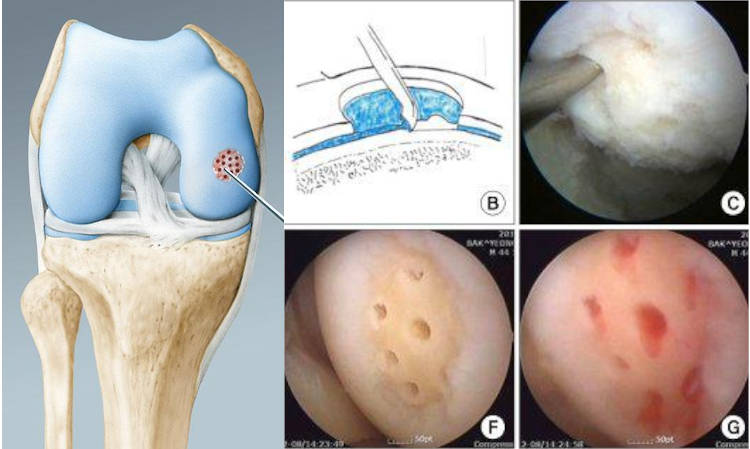

Τεχνική των μικροκαταγμάτων όπου με ειδικό εργαλείο δημιουργούνται μικρές οπές στο σημείο της βλάβης στο υποχόνδριο, ώστε να απελευθερώνεται αίμα πλούσιο σε αναγεννητικούς παράγοντες στο σημείο της βλάβης με αποτέλεσμα προοδευτικά να σχηματίζεται χόνδρος ινώδης στην περιοχή. Ο συγκεκριμένος χόνδρος δεν έχει τις ιδιότητες του υαλοειδούς χόνδρου είναι λιγότερο εύκαμπτος και ελαστικός. Η τεχνική δείνει να είναι αρκετά αποτελεσματική σε βλάβες χόνδρου μέχρι 2 εκατοστά και καλή ποιότητα υποχόνδριου ιστού.